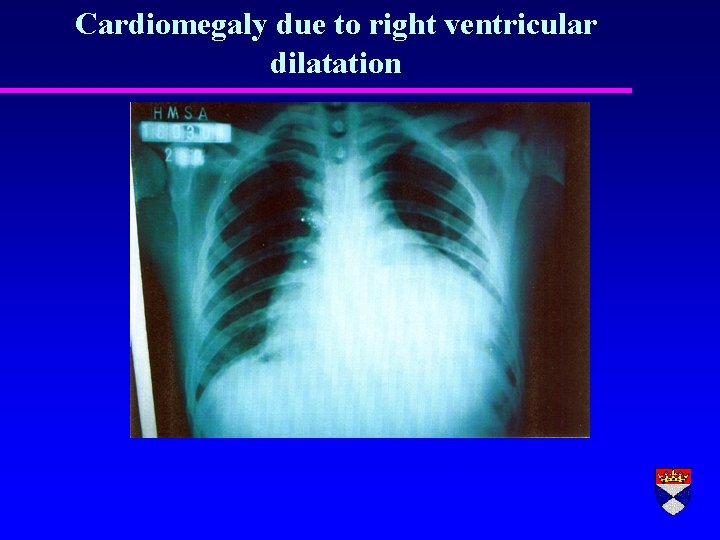

“Cor Pulmonale” r Pulmonary hypertension complicating lung disease r Right ventricular hypertrophy r Right ventricular dilatation r Right heart failure (swollen legs, congested liver etc)

Cardiomegaly due to right ventricular dilatation

Right ventricular hypertrophy and dilatation